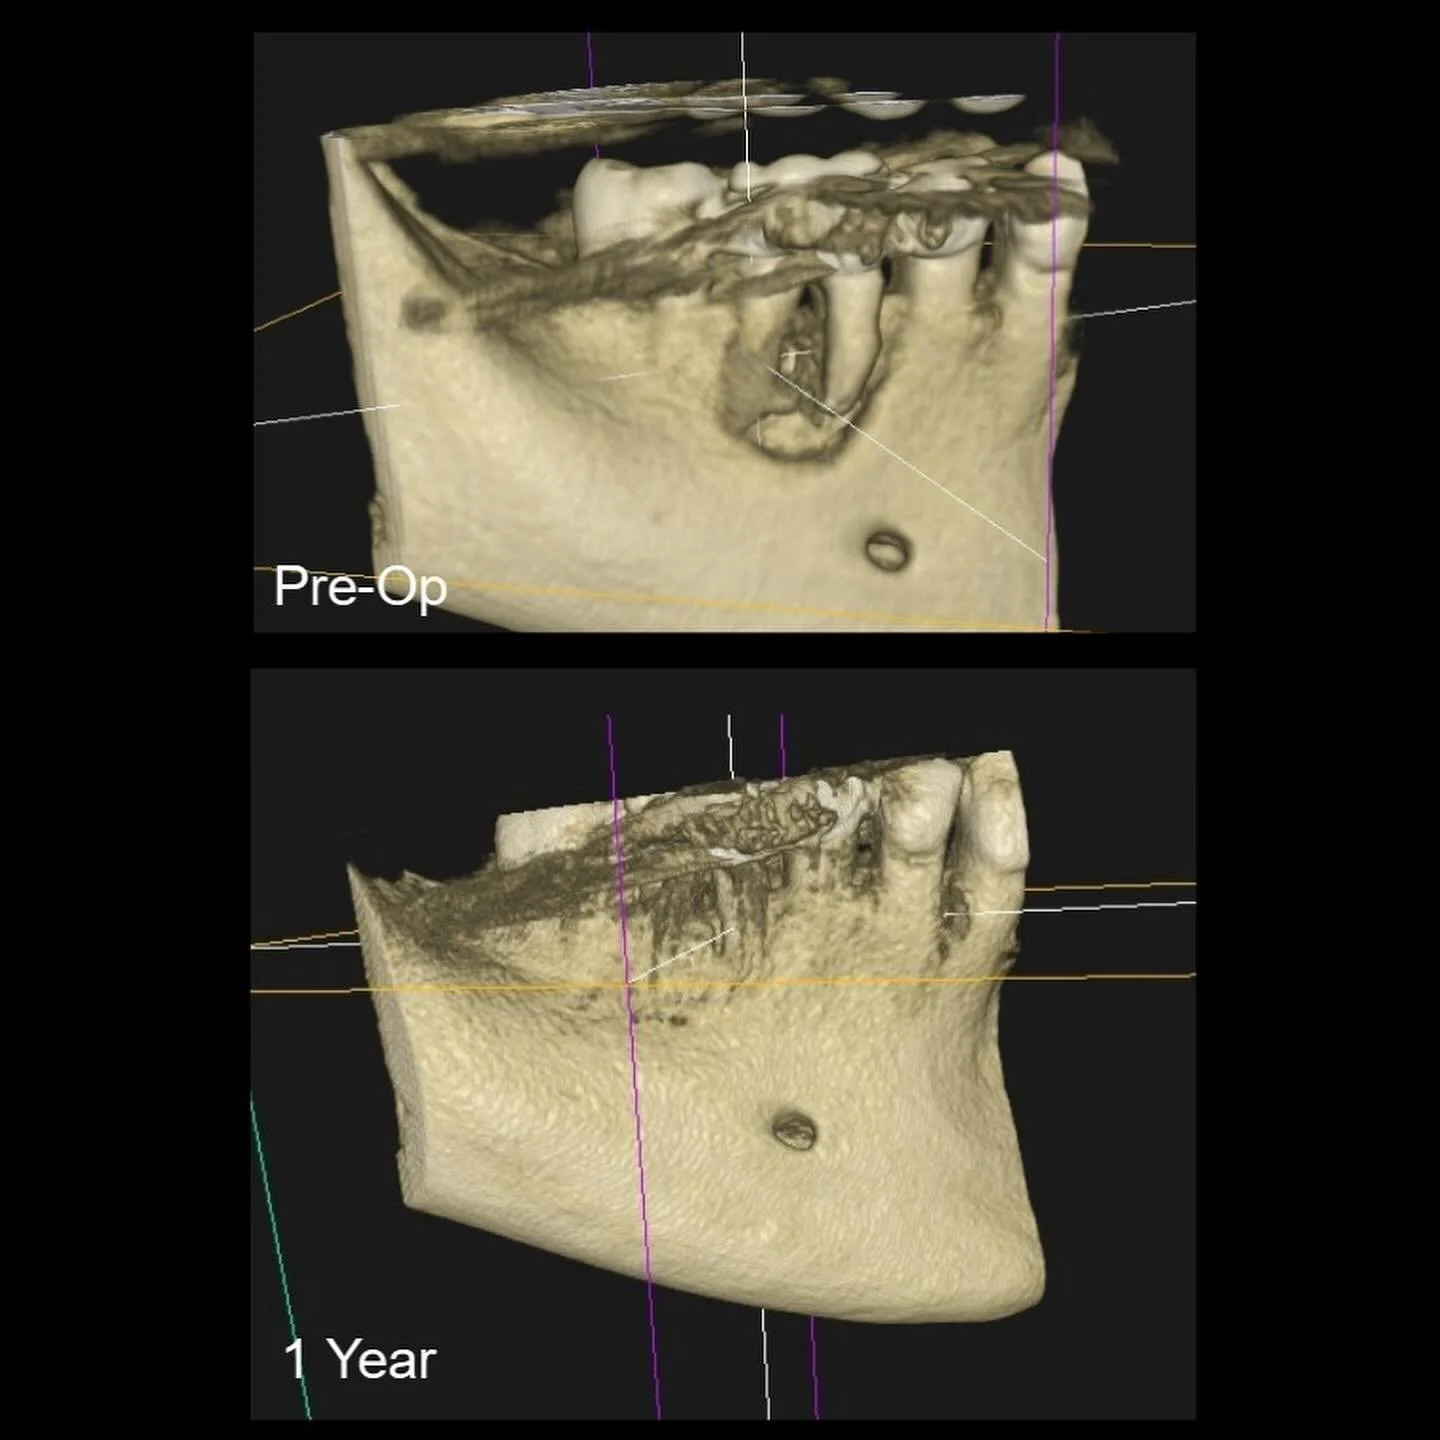

I am a board-certified endodontist with advanced specialty training and an academic interest in diagnostic reasoning, retreatment, and microsurgical endodontics. My work emphasizes CBCT-guided decision-making, interdisciplinary collaboration, and evidence-based care in complex clinical scenarios.